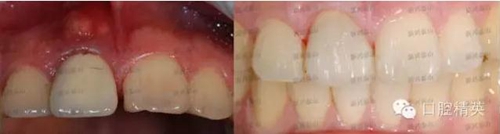

去掉烤瓷冠,去掉松動老式螺紋固位釘,其內(nèi)大量的腐爛牙質(zhì),治療之后,剩余牙體很少,如上圖所見。根管治療后,牙齒健康,膿包消失,可以進行后續(xù)的治療,讓患者拾回自信。

以前的老式螺紋固位釘根本就不行,早已淘汰。前牙的美觀要求高,采用3M的石英纖維樁,作為固位支撐連接整個牙體,即牙根和牙冠。這種纖維樁是透明的,透光性更好,光照時早期即可固化;彈性模量接近牙齒本身,更好的保護牙齒;形狀如同牙根的形態(tài),呈錐度,這樣避免了破壞大量健康牙質(zhì);固位靠粘結(jié)固位。

預備牙體形態(tài),過程中使用放大鏡,這樣預備的細節(jié)處理得更加精確。很遺憾,沒有照備牙之后的照片。硅橡膠二次取模法精準確定牙齒的模型,大大增強了牙齒的密合程度。